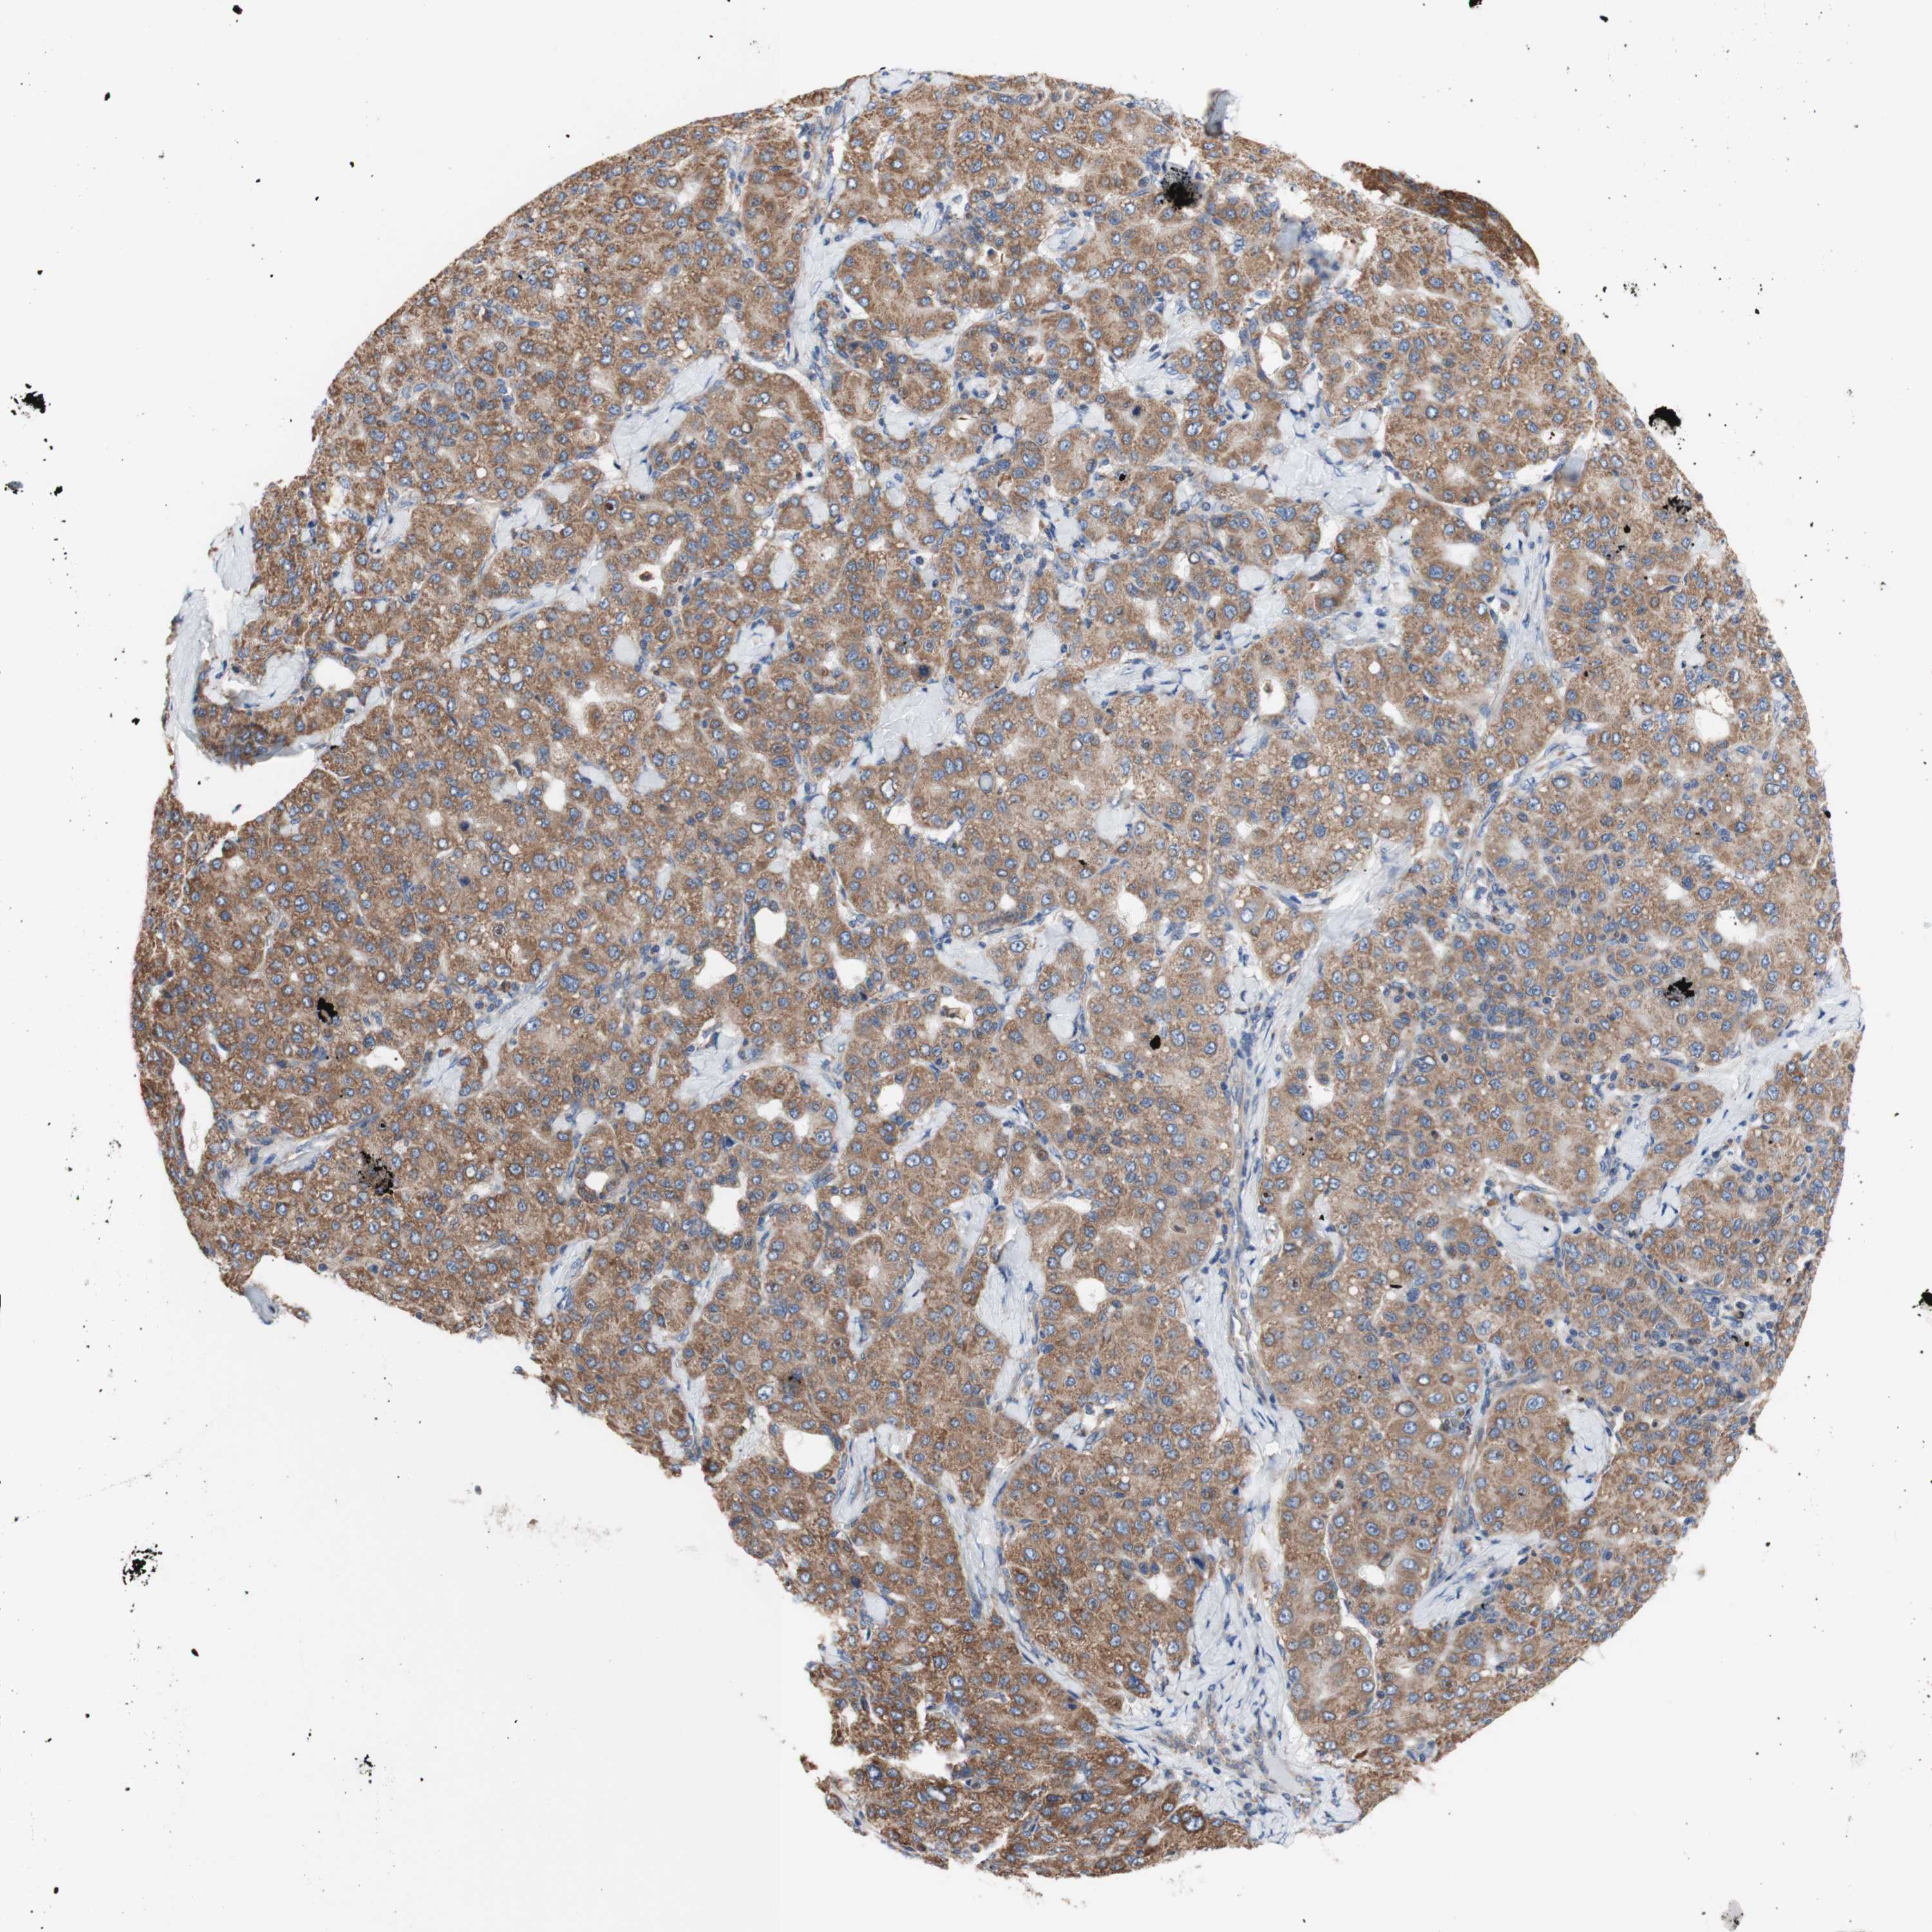

LIVER CANCER - Protein expressioni

A mouse-over function shows sample information and annotation data. Click on an image to view it in a full screen mode. Samples can be filtered based on level of antibody staining by selecting one or several of the following categories: high, medium, low and not detected. The assay and annotation is described here.

Note that samples used for immunohistochemistry by the Human Protein Atlas do not correspond to samples in the TCGA dataset.

Antibody stainingi

Antibody staining in the annotated cell types in the current human tissue is reported as not detected, low, medium, or high, based on conventional immunohistochemistry profiling in selected tissues. This score is based on the combination of the staining intensity and fraction of stained cells.

Each image is clickable and will lead to virtual microscopy that enables deeper exploration of all samples and also displays staining intensity scores, fraction scores and subcellular localization as well as patient and tissue information for each sample.

Antibody HPA050118

Antibody HPA056084

Antibody CAB012444

Staining

High

Medium

Low

Not detected

Intensity

Strong

Moderate

Weak

Negative

Quantity

>75%

75%-25%

<25%

None

Location

Nuclear

Cytoplasmic/membranous

Cytoplasmic/membranous,nuclear

Carcinoma, Hepatocellular, NOS

Cholangiocarcinoma